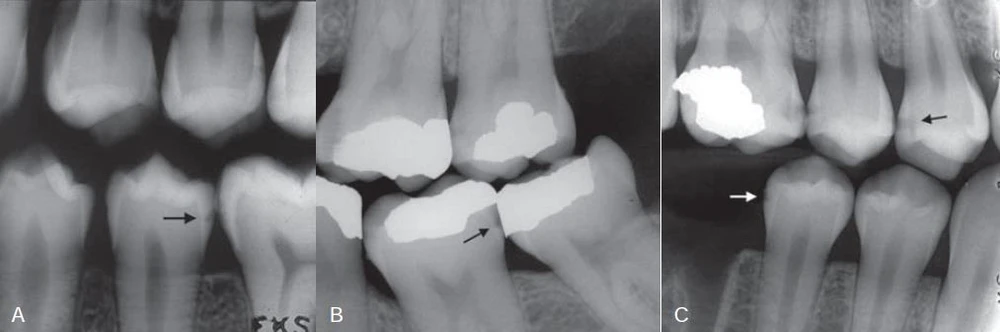

Hình 6. Phim cánh cánh thể hiện sâu răng mặt bên (mũi tên)

Hình 7. Sâu răng lan rộng vào phần ngà răng

Hình 9. Sâu răng ở răng cạnh răng mang miếng trám do quá trình tạo xoang trám làm tổn thương bề mặt răng kế cân.

Thậm chí những nha sĩ nhiều kinh nghiệm cũng thường không đồng ý với việc có hay không có sâu răng khi kiểm tra trên một lần chụp X quang khi tổn thương chỉ giới hạn ở phần men răng. Đôi khi có thể phát hiện sai tổn thương sâu răng khi bề mặt răng không bị ảnh hưởng (kết quả dương tính giả). Nhiều hiện tượng hình thái chẳng hạn như những trũng và rãnh, chỗ lõm vùng cổ răng, hiệu ứng dải Mach, những bất thường về răng chẳng hạn như những rãnh giảm sản và những chỗ lõm do mòn răng cũng có thể giả dạng hình ảnh sâu răng. Trong những trường hợp mất khoáng không biểu hiện rõ trên X quang, việc không phát hiện được thương tổn được gọi là kết quả dương tính giả. Ngoài ra, những điểm tiếp xúc chồng lên nhau trên hình ảnh X quang có thể che lấp mất tổn thương. Khoảng một nửa tất cả những tổn thương mặt bên ở phần men răng không thể phát hiện được trên X quang.

Hình 10. Những hình ảnh dương tính giả (mũi tên)